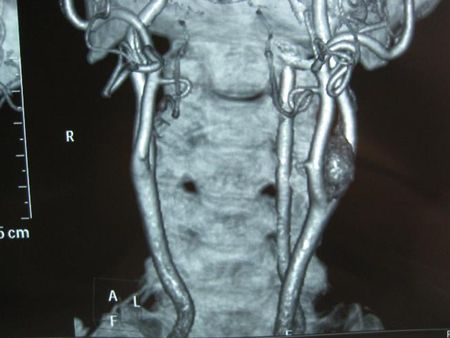

Su diagnóstico generalmente se realiza por la aparición de una masa lateral en el cuello

que a veces transmite el pulso de la arteria contigua. Mediante ECODOPPLER

podemos encontrar una masa que separa la bifurcación carotidea y llegar al diagnóstico definitivo mediante ANGIOTAC, ANGIORM O ARTERIOGRAFÍA.